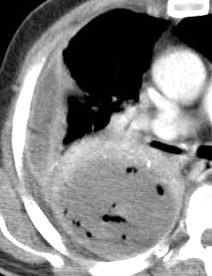

Signos radiológicos TC

Hallifax RJ et al. State-of-the-art: Radiological investigation of pleural disease Respiratory Medicine 2017

Nivel hidroaéreo o burbujas

Forma lenticular o elíptica Ángulos obtusos

> Grasa Extrapleural (60-80%)

Situación no gravitacional (no siempre)

Compresión de estructuras pulmonares

Límite muy bien definido Tabicación

Patrón ecográfico de empiema

Empiema

El derrame paraneumónico se convierte en complicado en 5-10% de los casos